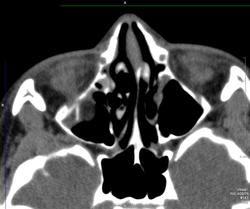

Перелом нижней стенки правой орбиты с проллабированием интра-орбитального жира в максилярный синус; на английском звучит как: "Tear drop fracture". При таких травмах может случится опущение глазного яблока, тогда необходимо оперативное вмешательство.

Такой перелом еще называется orbital blow-out fracture, не помню перевод, кажется взрывной перелом.

Респект, blow-out orbit Fx, этот термин также применяется при такой травме! Спасибо за публикацию!